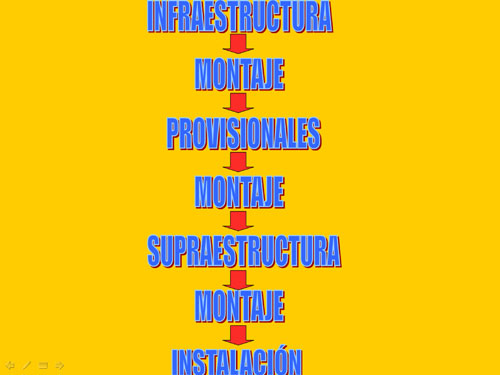

Infraestructura: tratamiento de los tejidos enfermos, de anatomía subyacente y reemplazo de raíces perdidas mediante Operatoria Dental, Endodoncia, Ortoncia, Periodoncia, Implantología, etc.

Montaje de la infraestructura: arco facial / articulador.

Instalación de nuevos provisionales (D.AT.O): En base al encerado y tratamiento de la guía anterior, tratamiento de las tablas premolar- molar y tratamiento gingival concomintante. Espera prudencial en provisionales.

Montaje de la infraestructura: arco facial / articulador para construir la Supraestructura.

Supraestructura (D.AT.O.): Tratamiento de la Guía Anterior, Tratamiento de las Tablas Premolar Molar.

Montaje de la supraestructura: arco facial / articulador (remonta).

Ajuste final de la oclusión (D.AT.O.)